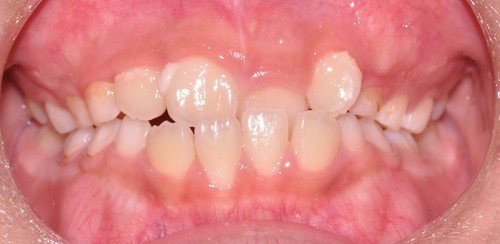

タイプⅢは受け口や交叉咬合に使います。大人の場合は顎の成長が止まっているので、反対咬合・受け口の場合は歯の軸を変えて治す場合と遺伝的に下顎そのものが大きい場合は外科手術で下顎の骨を切って治す場合があります。小児の場合は、まだ下顎の成長が始まっていないので、できるだけ上顎を積極的に成長させなければなりません。受け口・反対咬合だと、下の前歯が上の前歯の前にあるので、上の顎が前方に成長するのを妨げてしまうので、受け口だったら出来るだけ早くに改善する必要があります。下の写真のように短期で改善することが出来ます。

↓

最初から8カ月で受け口は改善していますし、さらに歯と歯の間に隙間が生じているので歯列が拡大しているのが分かります。